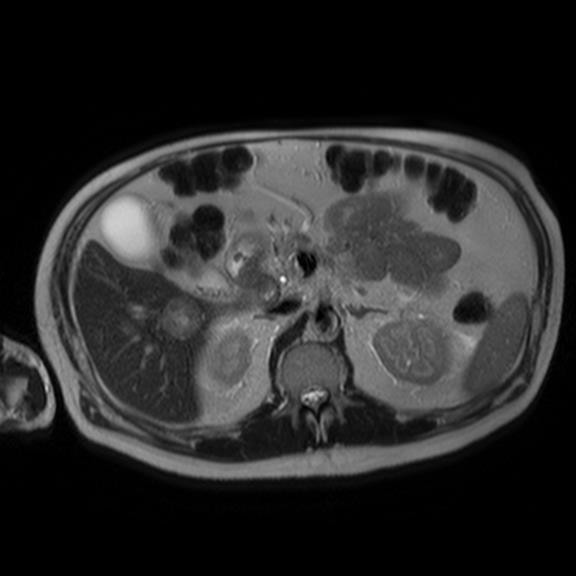

Nearly 11 months after his initial presentation, the patient presented again to his doctor for another follow up. At that point it was clear that the patient was declining rapidly. The rash had spread to his perineum and groin. He described the rash as excruciatingly painful to the point where the patient needed a wheelchair to ambulate. Upon further questioning, the patient reported a thirty pound weight loss over the prior 4 months. He still endorsed the diarrhea. A closer examination of his mouth and oral mucosa revealed dry, cracked and inflamed lips. The patient stated he had noticed this for about a year but did not make much of it. Lab work showed a new normocytic anemia with Hemoglobin of 11.4, an albumin of 2.8, and ESR of 63, and a blood sugar of 165. A malignancy work up was started at this point. CT of his abdomen revealed a pancreatic tail mass as well as three focal liver lesions which were confirmed on MRI (Figures 2-4).

Figure 3 Abdominal MRI showing pancreatic tail mass.